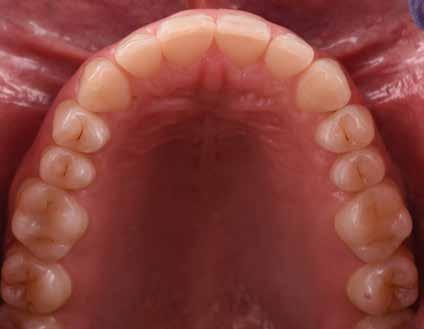

B.M. Bambina di sei anni e mezzo, con malocclusione scheletrica di II Classe, deep-bite over-jet elevato, lieve contrazione dell’arcata superiore, alterazione dell’eruzione dell’elemento dentale 21.

Fig. 125 > Immagine occlusale superiore.

Fig. 126 > Immagine occlusale inferiore.